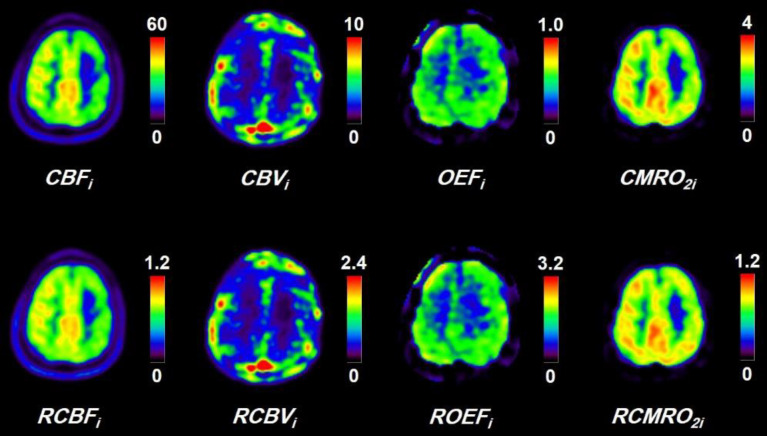

Methods: The CBF, CBV, OEF, and CMRO2 were measured in patients with occlusive cerebrovascular disease by PET using 15O-labeled gases, C15O2, C15O, and 15O2, with the steady-state method. In the present method, the ratios of values in a brain region to the reference region for CBF, CBV, OEF, and CMRO2 were calculated without invasive arterial blood sampling.

Results: Good correlations were observed for the ratios of values of the cerebral lesion to the reference brain region for CBF, CBV, OEF, and CMRO2 calculated by the present method as compared with those obtained by the steady-state method with arterial blood sampling, indicating its validity. Simulation studies showed that errors in estimated values calculated by the present method were negligibly small for both conditions of misery perfusion and matched hypoperfusion.